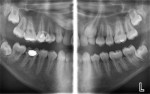

Some clinicians are not aware that they can take high-resolution (7-8 line pairs/mm) extraoral/panoramic bitewings. Dentists with pediatric patients may never have to put another image receptor in a child’s mouth again, and periodontists can take vertical bitewings without positioning problems. This is because several manufacturers now make panoramic machines that have bitewing programs. The disadvantage of the panoramic image for caries detection in the past has been inadequate line pair resolution and overlap of the contact points in the bicuspid regions. These deficiencies are now a thing of the past. One manufacturer (Planmeca, www.planmecausa.com) offers a patented technology called Selectively Compliant Articulating Robotic Arm (SCARA). The only machine to have a C arm on the top of its carriage, the bitewing acquisition is done robotically, with the patient in a typical panoramic position and the carriage moving inward toward the patient with a different start position to open contacts on most patients (Figure 1 through Figure 5). Of course, as with any dentition, if the tooth is ectopic or rotated, an additional image may be necessary to open the contacts. However, the quality of the image and ease of acquisition make this a very attractive technology. Looking carefully at the images, it is apparent that they are not only high-quality interproximal bitewing X-rays, but also high-quality periapical images from the canine to the molar region. Thus, with a digital panoramic machine capable of bitewing projections and producing excellent initial periapical views, the dose to the patient will be lower in most cases by eliminating unnecessary intraoral images. Although it is not a replacement technique, several dental schools in North America—including the Arizona School of Dentistry & Oral Health (ASDOH)—have adopted the protocol of using a panoramic and the extraoral panoramic bitewing/periapical projection as their initial radiographic examination. In addition, offices using this approach will find that there are fewer retakes and, therefore, less staff frustration related to radiographic procedures. At ASDOH, it has been found to reduce the number of full-mouth X-ray series, and intraoral and supplemental bitewing X-rays are needed only when indicated by selection criteria.

In addition to the possible reduction or even elimination of intraoral images for certain pediatric patients, the examples provided indicate that periodontists requiring vertical bitewings may also be interested in these contemporary panoramic machines.